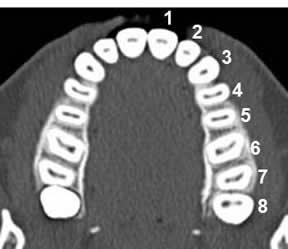

Cada cuadrante contiene 8 dientes y se enumeran de forma creciente, empezando por la línea media y en dirección distal. Las decenas indican el cuadrante y las unidades, la situación del diente en el cuadrante. (6, 8). (Fig 11).

Fig 11. Numeración de las piezas.

TAC axial. Numeración ascendente de proximal a distal.

1: Incisivo medial.

2: Incisivo lateral.

3: Canino.

4: 1º premolar.

5: 2ª premolar.

6: 1º molar.

7: 2º molar.

8: 3 molar.